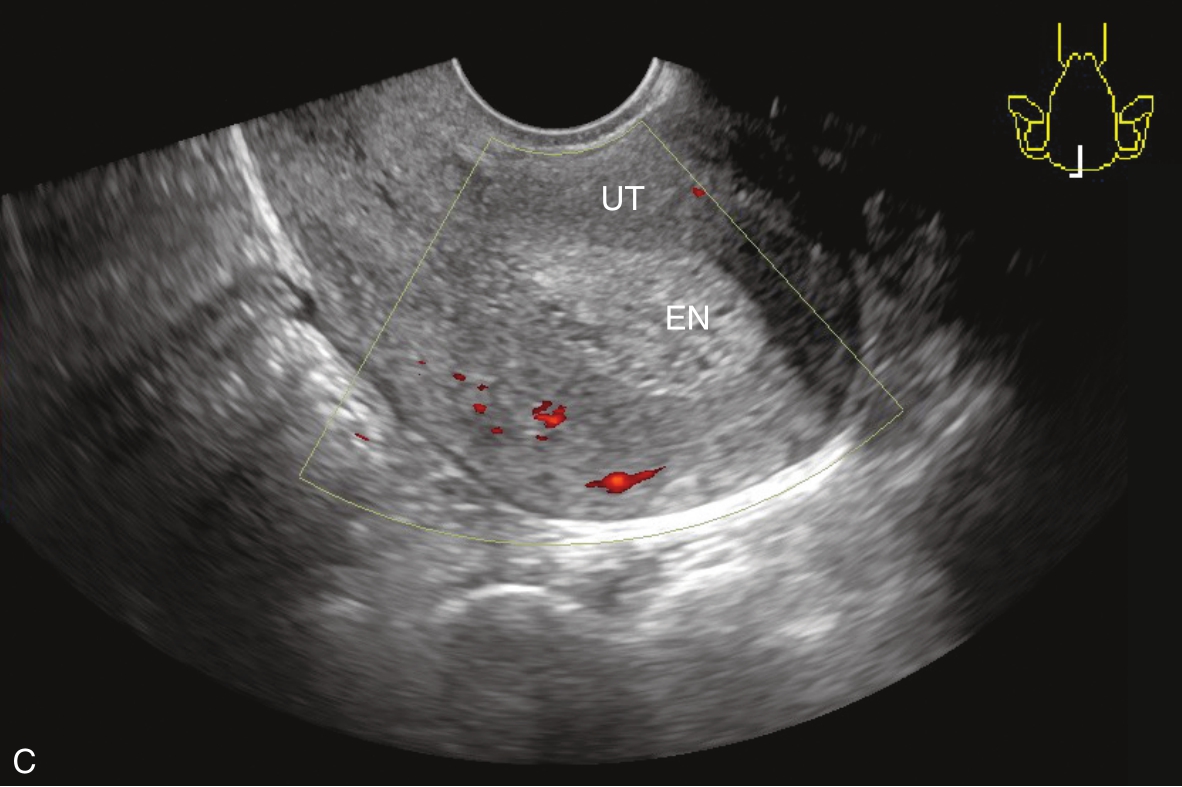

经阴道超声检查见图3-5-1。子宫后位,宫体大小约5.8cm×5.0cm×5.1cm,宫内膜厚约0.75cm(单层),内膜回声不均匀。宫腔未见分离。宫壁回声均匀。内膜内见多个囊性结节,较大者大小约0.5cm,内透声可。CDFI:未见异常血流信号。双侧附件区未见异常回声。盆腹腔未见明显积液。超声检查结果:宫内膜增厚伴回声不均匀。

图3-5-1 常规超声声像图

A.后位子宫的矢状切面(经阴道),子宫内膜增厚,单层厚约0.75cm,内见多个小暗区;B.后位子宫的横断面(经阴道);C.后位子宫的矢状切面(经阴道),彩色多普勒能量图超声检查显示子宫未探及明显血流信号;D.右卵巢;E.左卵巢。UT:子宫;EN:子宫内膜;R-OV:右卵巢;L-OV:左卵巢。